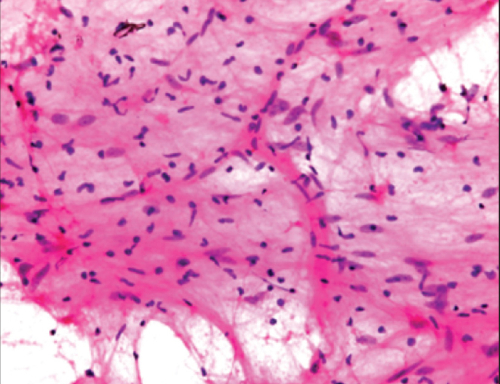

Cytopathology is also commonly used to investigate thyroid lesions, diseases involving sterile body cavities (peritoneal, pleural, and cerebrospinal), and a wide range of other body sites. It is usually used to aid in the diagnosis of cancer, but also helps in the diagnosis of certain infectious diseases and other inflammatory conditions.